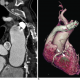

Her açıdan en yüksek dansite değerine sahip voksellerin birleştirilerek iki boyutlu görüntüye aktarılması ile oluşturulur. Vaskuler yapıların görüntülenmesinde oldukça sık olarak kullanılan MIP görüntülemenin dezavantajı daha düşük dansiteye sahip voksellerin baskılamasıdır.

Bu nedenle yumuşak plaklar, lümendeki kontrast madde tarafından; lümen içi kontrast madde de kalsifiye plaklar tarafından baskılanır ve stenoz oranı olduğundan daha fazla yorumlanır. Toraks BT’de vaskuler yapıların görüntülenmesi dışında MIP görüntülemenin diğer en önemli avantajı ise akciğer nodüllerinin saptanmasını kolaylaştırmasıdır.

Transvers görüntüler ile karşılaştırıldığında MIP görüntüler ile daha fazla sayıda nodül saptandığı ve nodüllerin dağılımının daha iyi gösterildiği anlaşılmıştır.

(A) Maximum Intensity Projection görüntülerde nodüllerin daha göze çarptığı ve nodül saptanmasını kolaylaştırdığını görmekteyiz. (B) Minimum Intensity Projection görüntülerde ise hava hapsi alanları daha belirgin olarak izlenmektedir.